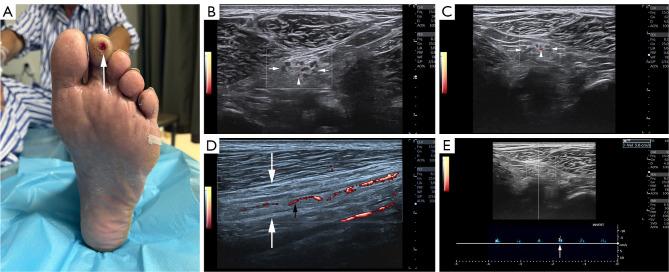

Intraneural blood flow (INBF) serves as a useful marker for diagnosing peripheral neuropathies. However, the specific relationship between sciatic nerve INBF (SN) and the occurrence of diabetic peripheral neuropathies (DPNs) and diabetic foot ulcers (DFUs) remains ambiguous. Thus, the purpose of this study was to investigate the association between SN, as detected by power Doppler ultrasound, and the presence of DPNs and DFUs in patients with diabetes.

A retrospective cross-sectional study was performed on patients with diabetes between June 2018 and July 2024. The study population was categorized into two groups based on electroneurophysiological findings: a DPN and a non-DPN group. Within the DPN group, the patients were subdivided as DFU and non-DFU subgroups. Clinical characteristics and ultrasound parameters, including SN, were compared between those groups and subgroups. Logistic regression analysis was employed to investigate the relationships between SN and the presence of DPN and DFU. Additionally, the diagnostic performance of SN was assessed through the areas under the receiver operating characteristic curves (AUROCs) for identifying DPN and DFU. Meanwhile, sciatic nerves (SNs) of healthy controls (HCs) were taken as normal controls to determine whether SN can be detected in HC by power Doppler ultrasound.

The study included 113 patients with diabetes [mean age ± standard deviation (SD), 63.81±12.31 years; 71 males] (82 had DPN and 31 did not). The subgroup analysis of DPN patients included 61 individuals with DFU and 21 without. Adjusted logistic regression analysis revealed a significant independent association between SN and the presence of DPN in patients with diabetes [odds ratio (OR): 7.399; 95% confidence interval (CI): 1.959-27.944; P=0.004]. Further analysis within the DPN subgroup confirmed a significant association between SN and the presence of DFUs (OR: 12.255; 95% CI: 2.881-52.135; P=0.001). The AUROC for SN in diagnosing DPN and DFU was 0.755 and 0.727, respectively (all P<0.05), with corresponding sensitivities and specificities of 67.1% and 83.9% for DPN and 78.7% and 66.7% for DFU, respectively. Additionally, there were 19 HCs (38 SNs, matched gender and age with patients with diabetes). Among those HC, no SN was detected by power Doppler ultrasound.

SN is positively correlated with DPN in patients with diabetes and with DFU in those with DPN, suggesting that SN is a valuable indicator for diagnosing both DPN and DFU.